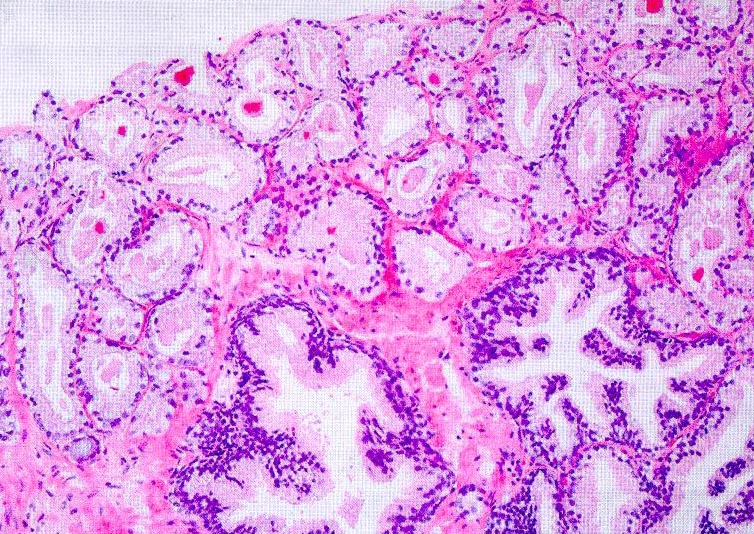

8/97 evaluation by Dr. Jonathan Oppenheimer (Oklahoma) of one of the biosy cores (taken 7/2/97 and shown to the right) indicated Gleason grade 2+2 or 2+3 and was consistent with a transition zone tumor.

9/10/97 evaluated by Drs. Thomas Stamey and John McNeal, Stanford: "one of the three biopsies (15, 9, and 11 mm) from the right side had 2 mm of clear cell cancer Gleason grade 3+3".